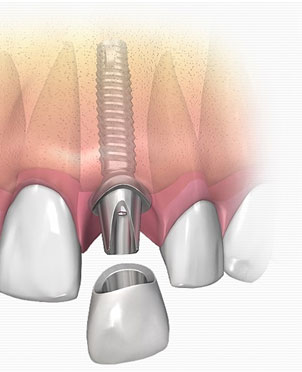

Dental Implants in Karachi: What You Actually Need to Know

Losing a tooth changes more than you expect. It's not just about the gap in your smile, though that's uncomfortable enough on its own. It affects how you chew, how you speak, how confident you feel in a conversation, and over time, it can affect the health of the surrounding teeth and jawbone in ways [...]

Dental Implants at Altamash Dental Clinic: Smiles Re-made, Confidence Restored

We’ll all sooner or later, at one time or another, lose a few teeth here and there, to decay, to an accident, or just to wear and tear

Smile Strong: Why Dental Implants Are the Gold Standard in Tooth Replacement

Missing teeth not only affect your appearance—they also impact your speech, eating, and confidence. At Altamash Dental Clinic, we believe everyone deserves a full, confident smile. Dental implants offer a natural-looking, permanent solution that feels just like real teeth. In this article, we will discuss what implants are, the benefits they offer, and why Altamash [...]

Why Dental Implants by Altamash Dental Clinic are the Best Option for Your Smile

Lost teeth can ruin your smile, besides ruining your self-confidence, oral well-being, and quality of life. Dental implants offer a permanent way to revive your smile and function. Altamash Dental Clinic employs experts to provide high-quality implants tailored to your specific requirements. Whether you are missing a single tooth or many, our trained staff aims [...]

Say Goodbye to Gaps: Transform Your Smile with Dental Implants at Altamash Dental Clinic

With dental implants, a missing tooth in the oral cavity can now be restored using some of the most advanced prosthetic solutions.